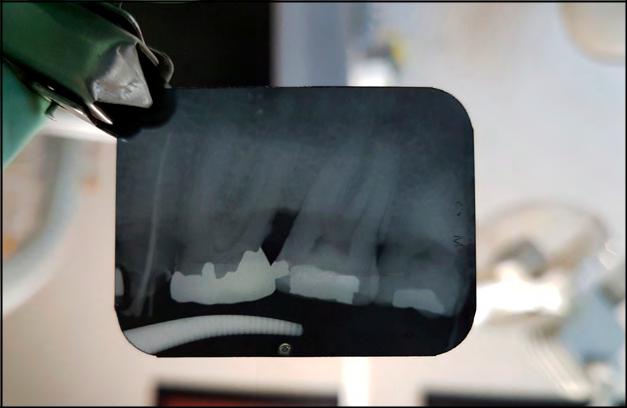

Dada la importancia del empleo de dicha radiación en el área dental y debido a que ha permitido la visibilidad de estructuras y ultraestructuras anatómicas densas, su empleo ha beneficiado al conocimiento y entendimiento patológico de tejidos no visibles por inspección simple. Sin embargo, y debido a que este tipo radiación (RI) puede causar alteraciones orgánicas en diferente grado, la presente revisión tiene como objetivo exponer su estado actual en el área odontológica, precisando el mecanismo de acción sobre órganos, tejidos, células y componentes celulares; su efecto nocivo sobre los mismos y, por último, evidencia las directrices para su empleo más apropiado en técnicas radiográficas bucodentales. Los criterios de inclusión de esta revisión contemplaron estudios aleatorios, que pretendían conocer los efectos de la exposición a la RI en odontología. La búsqueda se realizó en la plataforma de datos de PUBMED, sin límite de periodo de tiempo y se utilizaron las palabras clave: ionizing radiation, radio sensitization, dental radiology, X-rays.

La tecnología utilizada en las ciencias dentales para el aprovechamiento de la radiación ionizante ha mostrado un desarrollo impresionante en los últimos años, gracias a la aplicación digital sobre la imagen radiográfica por los rayos X. Sin embargo, al momento actual aún existen contradicciones acerca del tipo de radiografía a utilizar, al momento de llevar a cabo un diagnóstico. Algunos investigadores coinciden en que la radiografía panorámica debe utilizarse ampliamente para complementar el examen clínico, ya que es menos perjudicial que la realización de varias radiografías de tipo periapical (Cerqueira et al., 2004; White & Pharoah, 2004).